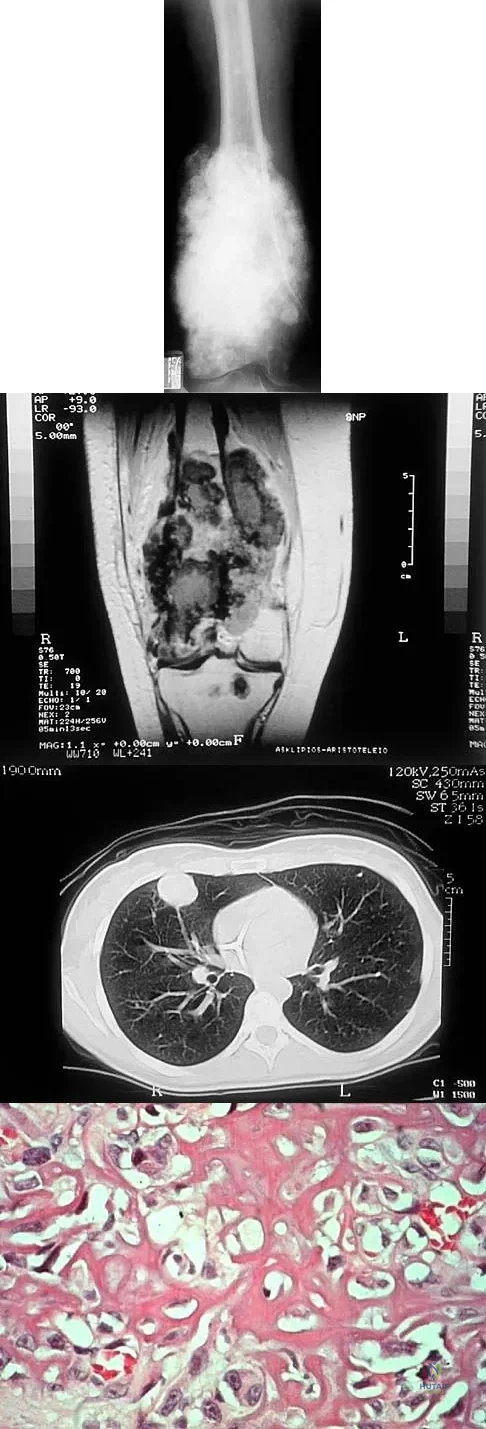

A 16-year-old girl has had painless swelling in her posterior left arm for the past 4 months. A radiograph, MRI scans, and an incisional biopsy specimen are shown in Figures 43a through 43d. What is the cytogenetic translocation most commonly associated with this tumor?

Explanation

This is a case of synovial sarcoma. The radiograph shows some soft-tissue swelling in the upper arm. The MRI scans show a lesion that has increased signal on T2-weighted images and low signal on T1-weighted images. There is a suggestion of a large cystic component to this lesion. The pathology shows a biphasic population of cells, a spindle cell component, and an epithelioid component. Up to 20% of synovial cell sarcomas have areas of cyst formation. The most common cytogenetic translocation with synovial cell sarcoma is X; 18. The 11; 22 translocation is most commonly associated with Ewing's sarcomas; the 12; 22 translocation is most commonly associated with clear cell sarcomas; the 2; 13 translocation is most commonly associated with alveolar rhabdomyosarcomas, and the 12; 16 translocation is most commonly associated with myxoid liposarcomas. Kawai A, Woodruff J, Healey JH, et al: SYT-SSX gene fusion as a determinant of morphology and prognosis in synovial sarcoma. New Engl J Med 1998;338:153-160.

A 19-year-old woman has a painful right knee. A radiograph, MRI scan, CT scan, and histopathologic specimen are shown in Figures 24a through 24d. What is the most likely oncologic stage of the lesion?

Explanation

The patient has a high-grade osteosarcoma of the distal femur with a skip lesion, and pulmonary metastasis is seen on the CT scan. This corresponds to a stage III lesion according to the Musculoskeletal Tumor Society System as adopted from Enneking.